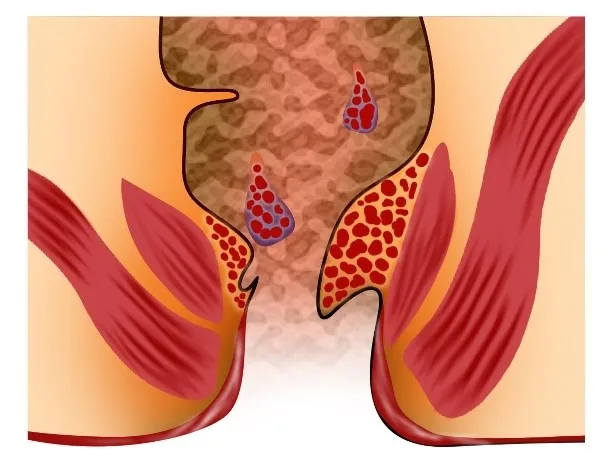

ਬਵਾਸੀਰ (ਹੈਮੋਰਾਇਡਸ) ਗੁਦਾ ਅਤੇ ਮਲਦਵਾਰ ਦੀਆਂ ਸੋਜੀ ਹੋਈਆਂ ਰਗਾਂ ਹਨ। ਅੰਦਰੂਨੀ ਬਵਾਸੀਰ ਨੂੰ 4 ਗਰੇਡਾਂ ’ਚ ਵੰਡਿਆ ਜਾਂਦਾ ਹੈ: